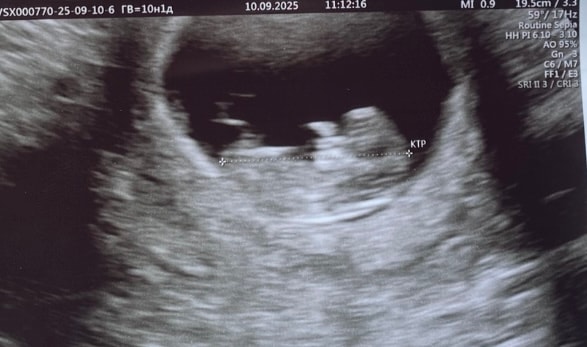

девочкиии привет милые🌸👋🏻 спешу с вами поделиться о том, что тот замер желточного мешочка 7,0 мм был ошибочным слава Богу!!🙏🏻😭😭 то то я точно помню, что узистка про него ничего не говорила, а просто значит этот размер был размером другого человека, который был до меня🤷♀️ сегодня сходила на узи и наш мешочек 4,9 мм на 10,2 недели🙌🏻🙌🏻 я

как раз закончилась тревога по отслойке и на тебе теперь этот мешочек🫠🫠🤌🏻🤌🏻🥹 нет чтобы жить спокойно нам🥲😂 а если серьезно, то врач узи сказала да, он чуть больше, но это норма и все показатели у вас в срок🤷♀️ в 9 недель он был 4,7 мм, но там смотрела другой узист. кто-нибудь сталкивался с таким размером ЖМ?🥹 поделитесь, пожалуйста 🙏🏻